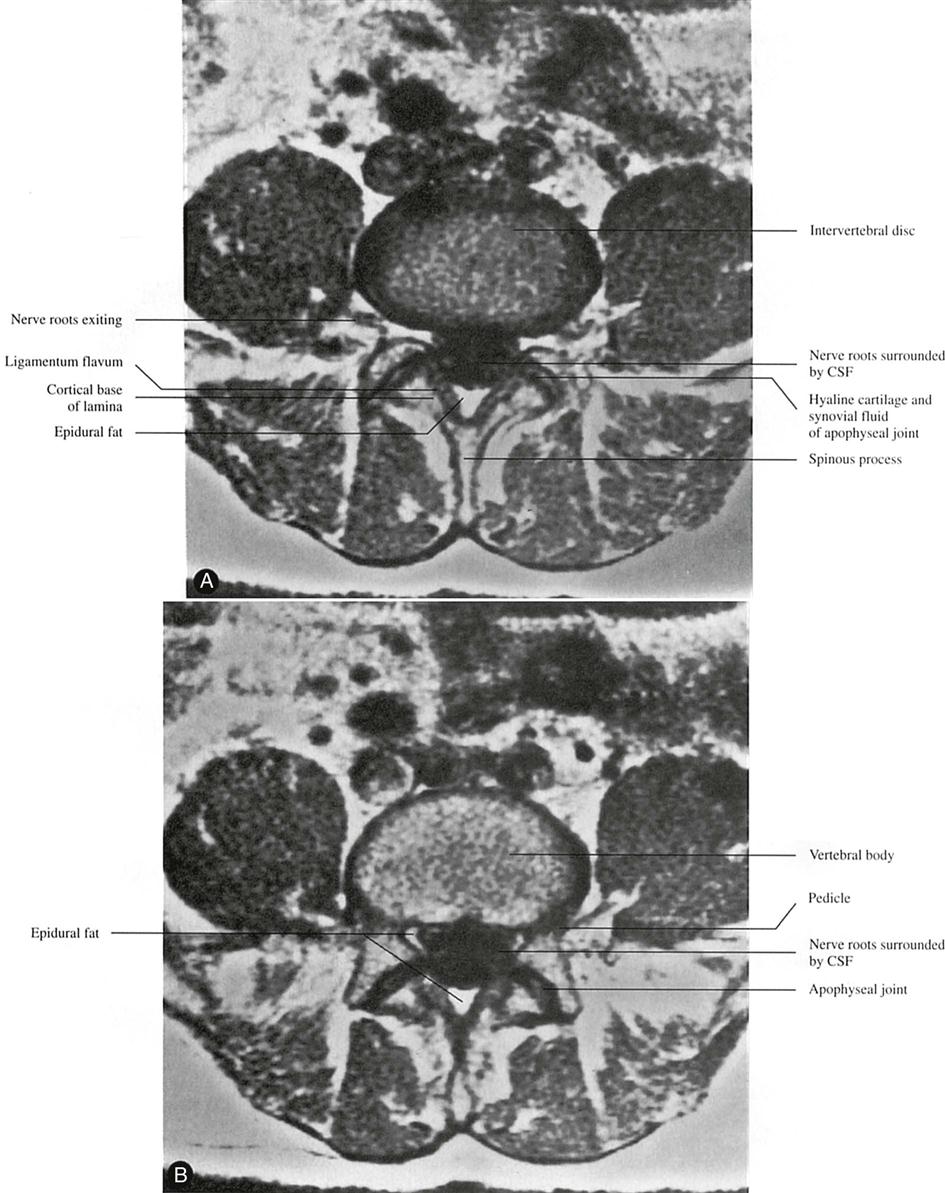

A CT scan may be used to delineate a fracture or to show the presence of spinal stenosis caused by protrusion or a tumor, or if a bony abnormality is suspected256 (Figures 9-116 through 9-119). As with plain x-rays, results must be correlated with clinical findings, because the anatomical changes seen are often unassociated with the patient's symptoms.255,264,265 This technique provides an axial projection of the spine, showing the anatomy of not only the spine but also the paravertebral muscles, vascular structures, and organs of the body cavity. In doing so, it shows more precisely the relation among the intervertebral discs, spinal canal, facet joints, and intervertebral foramina. It may be used to evaluate spinal stenosis, the shape of the spinal canal, epidural scarring (after surgery), facet joint arthritis, tumors, and trauma.124,266,267 It may be used in conjunction with a water-soluble contrast medium (computer-assisted myelography) to further delineate the structures.